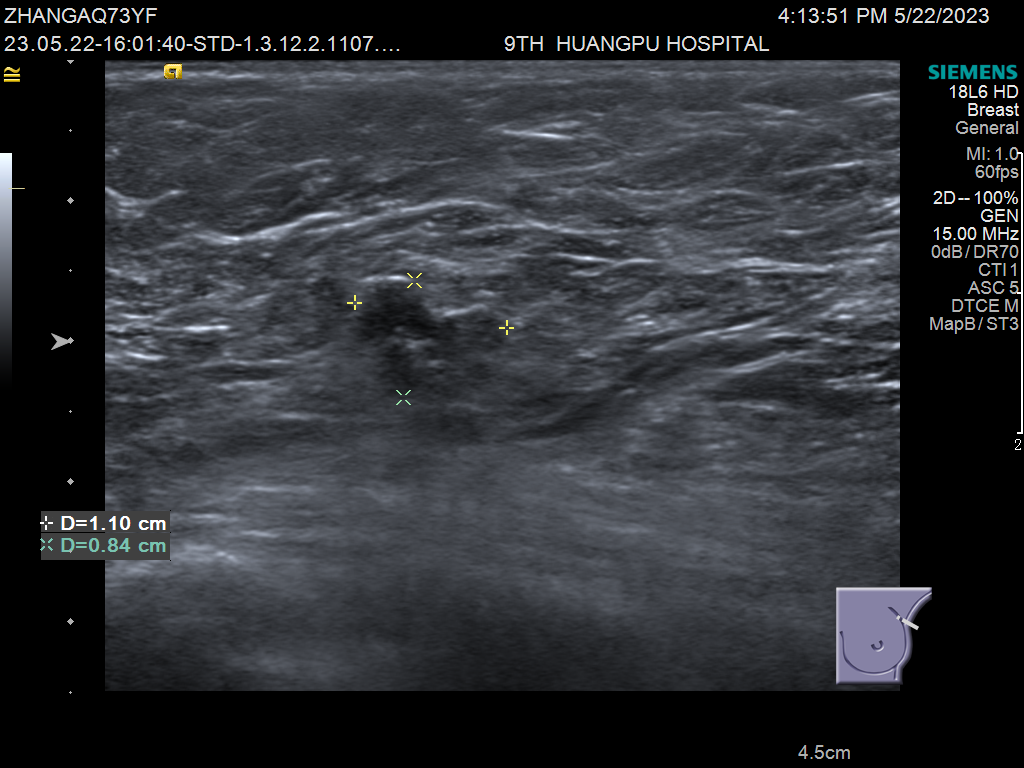

此病例为多病灶的浸润性乳腺癌患者,在手持式超声扫查时发现左乳头上方及外上方近乳腺边缘的两个病灶,术前磁共振检查发现三个病灶,再行ABVS检查,发现中间还有一个小子灶。入我院手术,病理证实小子灶为浸润性乳腺癌。

手持式超声扫查